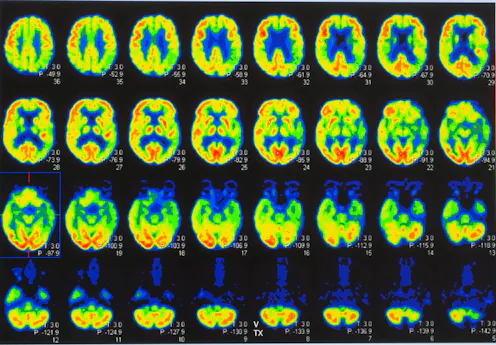

All participant had three brain scans: one to measure dopamine, one to measure serotonin, and another to study anatomical regions in the brain.

Comparing data from the different groups allowed us to measure the severity of dopamine and serotonin loss at different stages of the disease, from people without symptoms to people with a diagnosis. It also allowed us to compare changes seen in the gene carriers with changes seen in those with sporadic Parkinson’s disease. This helped us translate our findings in the gene carriers into the more common sporadic form of Parkinson’s disease.

We discovered that gene carriers without symptoms had depleted serotonin, while their dopamine neurons appeared to remain intact. So the changes in the serotonin system that we identified are likely to start very early and precede the onset of motor symptoms by some years.